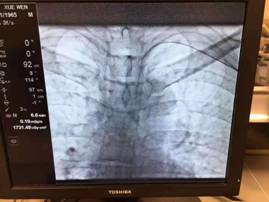

54岁的左某是一例无法手术的肝癌患者,经肝动脉的化疗栓塞术是目前延续此类患者生命的首选方案。为保证疗效,介入手术需反复进行,同时传统方法需要在股动脉穿刺建立治疗通路,手术后需压迫大腿根部穿刺点,同时患肢必须伸直,6—8个小时不能活动。术后的漫长卧床过程让左某记忆犹新,对即将再次接受的介入治疗充满恐惧感。

如何解决肝癌介入术后的这个“老大难”问题也成为介入团队的攻关目标之一。团队通过反复查阅文献和与国内外同行的广泛交流学习,发现通过手部的桡动脉穿刺,即可有效解决左某的顾虑。但该途径的穿刺血管很细,穿刺成功率低;最难的地方还在于这种治疗路径与传统治疗路径完全相反,对医生的操作技巧要求极高。患者利益至上是二院肝胆外科人的首要目标。介入团队医生们将该手术难点逐点分解攻破,并反复演练,终于掌握了这一方法。10月31日,由游科医生主刀,幸运的左某成为该技术的第一位获益者。一个半小时后,左某自己走下手术床,然后步行回到肝胆外科病房,于11月1日出院回家。

众所周知,肝动脉化疗栓塞术(TACE术)是肝癌治疗的有效、微创手段。其操作原理将导管选择性或超选择性插入到肝脏肿瘤供血靶动脉后,注入适量的栓塞剂,使靶动脉闭塞,从而“饿死”肝肿瘤细胞。手术过程中,医生们通过采用注入抗癌药物或药物联合微粒、微球等方式起化疗性栓塞作用,最终达到“杀死”现有肿瘤的效果。

了解一下,传统的TACE术——经股动脉入路

主流手术方式是通过股动脉穿刺插管至肝动脉,在目标血管处栓塞、注射栓塞剂。其最突出的问题就是患者术后需行股动脉压迫8小时。这很大程度上增加了患者术后不适感(患者躺在床上8小时,不能活动,甚至不能翻身),影响了患者术后康复速度,延长了患者的住院时间,从而增加患者的经济负担。